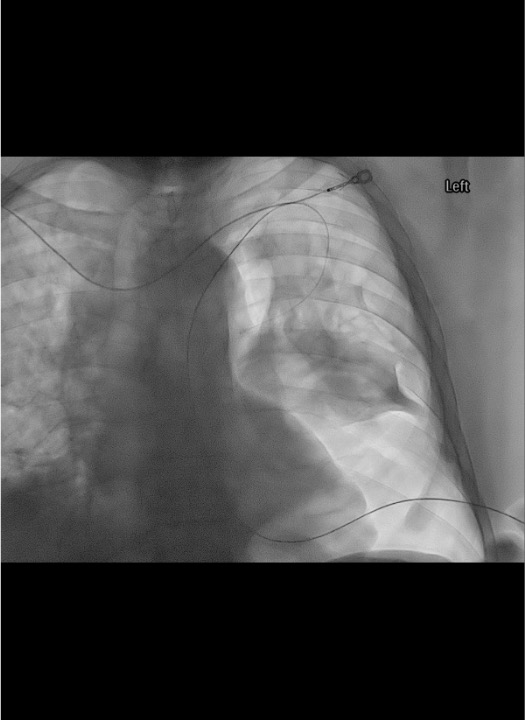

- Pleural fluid (gravity-dependent): Enter posterolateral at 4th–5th ICS posterior axillary line; orient tube posteroinferiorly. In supine patient, fluid collects posteriorly. Guide tip toward spine on AP fluoro, confirm stays close to spine on oblique view.

Catheter placement

Connect and confirm

Post-placement CXR